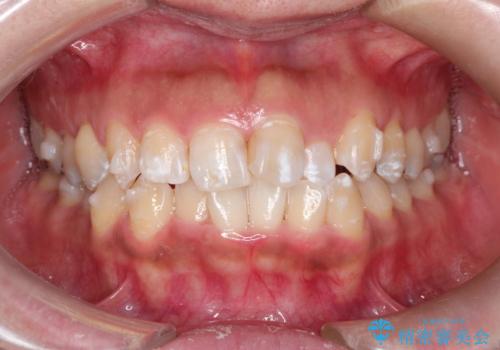

前歯のガタつきをマウスピース矯正で改善! 驚きの効果を体験しよう

- 前歯のガタツキが気になると来院されました。

奥歯の噛み合わせは綺麗に噛んでいたため、前歯の叢生(でこぼこ)に集中して治療するように計画しました。

奥歯の噛み合わせは整っていたため、前歯の並びを美しく修正することに専念できました。